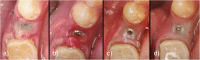

Methods: After randomization, 31 fully threaded titanium implants were inserted in 31 patients (16 men and 15 women) in the lower mandible using a split-flap technique. In the test group (10 patients), mucosa was treated with a PRF membrane. In the control group (21 patients), implantation was realized without soft tissue augmentation. Tissue thickness was measured at point of implant insertion (baseline) and at time of reentry after 3 months. Standardized digital radiographs were obtained for evaluation at time of implant placement, reentry after 3 months and at a 6-month follow-up. Data was analyzed by an independent examiner.

Results: After 6 months, all 31 implants were osteointegrated. Soft tissue augmentation with PRF led to a significant tissue loss. In the test group, the crestal tissue thickness dropped from 2.20 mm ± 0.48 SD at baseline to 0.9 mm ± 1.02 SD at reentry, whereas crestal mucosa in the control group showed higher stability (2.64 mm ± 0.48 SD at baseline to 2.62 mm ± 0.61 SD at reentry). For ethical reasons, the test group was terminated after 10 cases, and the remaining cases were finished within the control group. In the test group, radiographic evaluation showed a mean bone loss of 0.77 mm ± 0.42 SD/0.57 mm ± 0.44 SD (defect depth/defect width) on the mesial side and 0.82 mm ± 0.42 SD/0.62 mm ± 0.36 SD (defect depth/defect width) on the distal side. In the control group, a mean bone loss of 0.72 mm ± 0.61 SD/0.51 mm ± 0.48 mm (defect depth/defect width) on the mesial and 0.82 mm ± 0.77 SD/ 0.57 mm ± 0.58 SD (defect depth /defect width) on the distal side was measured.